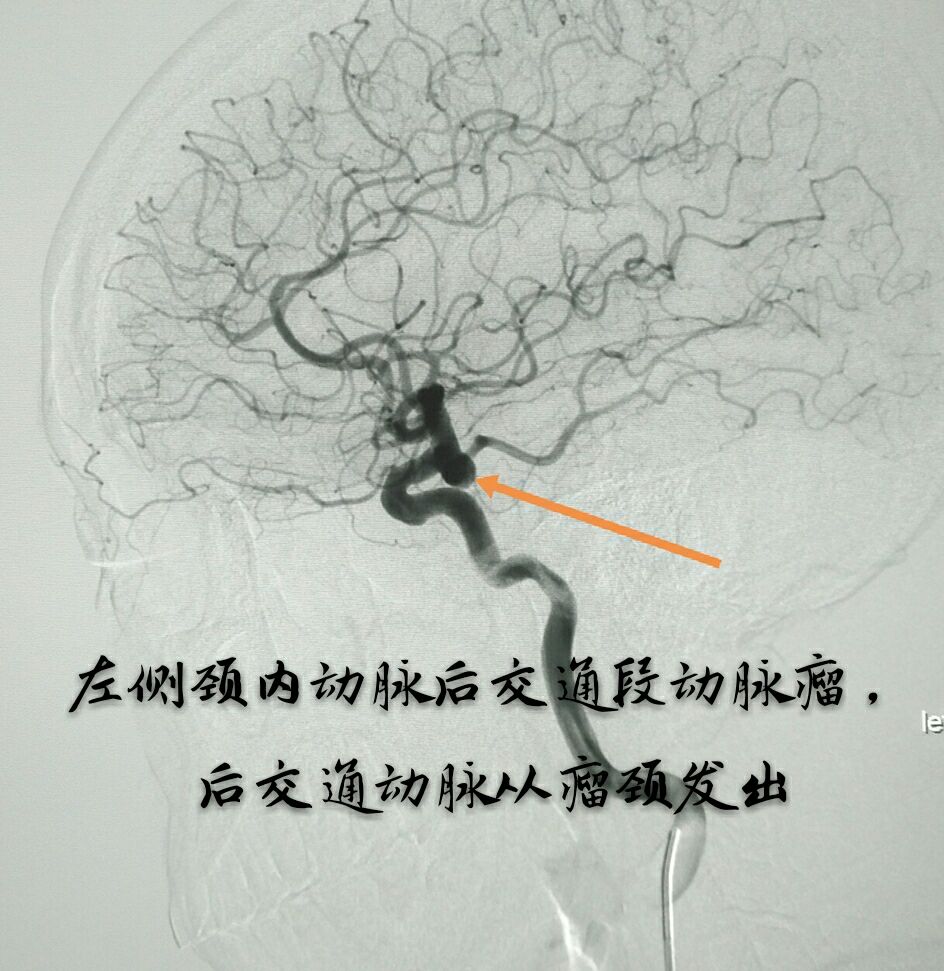

病例十:老年男性患者,间断性头痛1年,DSA示左侧颈内动脉后交通段动脉瘤,后交通动脉从瘤颈部发出

支架打开,首圈完美成栏

最终动脉瘤致密栓塞,载瘤动脉及后交通动脉通畅